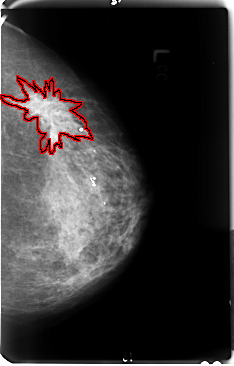

B_3048_1.LEFT_MLO

FILE: B_3048_1.LEFT_MLO.OVERLAY

TOTAL_ABNORMALITIES 1

ABNORMALITY 1

LESION_TYPE MASS SHAPE IRREGULAR-ARCHITECTURAL_DISTORTION MARGINS ILL_DEFINED-SPICULATED

ASSESSMENT 4

SUBTLETY 4

PATHOLOGY MALIGNANT

TOTAL_OUTLINES 1

BOUNDARY